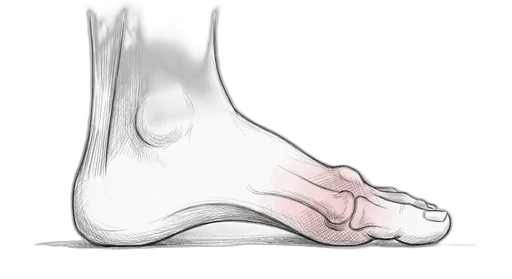

Foot & Ankle Exercise Guide

Choose your condition below to get started with exercises and stretches designed by Dr. Patish.

Pick your condition below, and you'll find your personalized exercise program — with medical illustrations, step-by-step instructions at three intensity levels, and clear guidance on when to call our office. Every protocol here is the same one Dr. Patish prescribes to patients in the clinic.

Forefoot & Toes